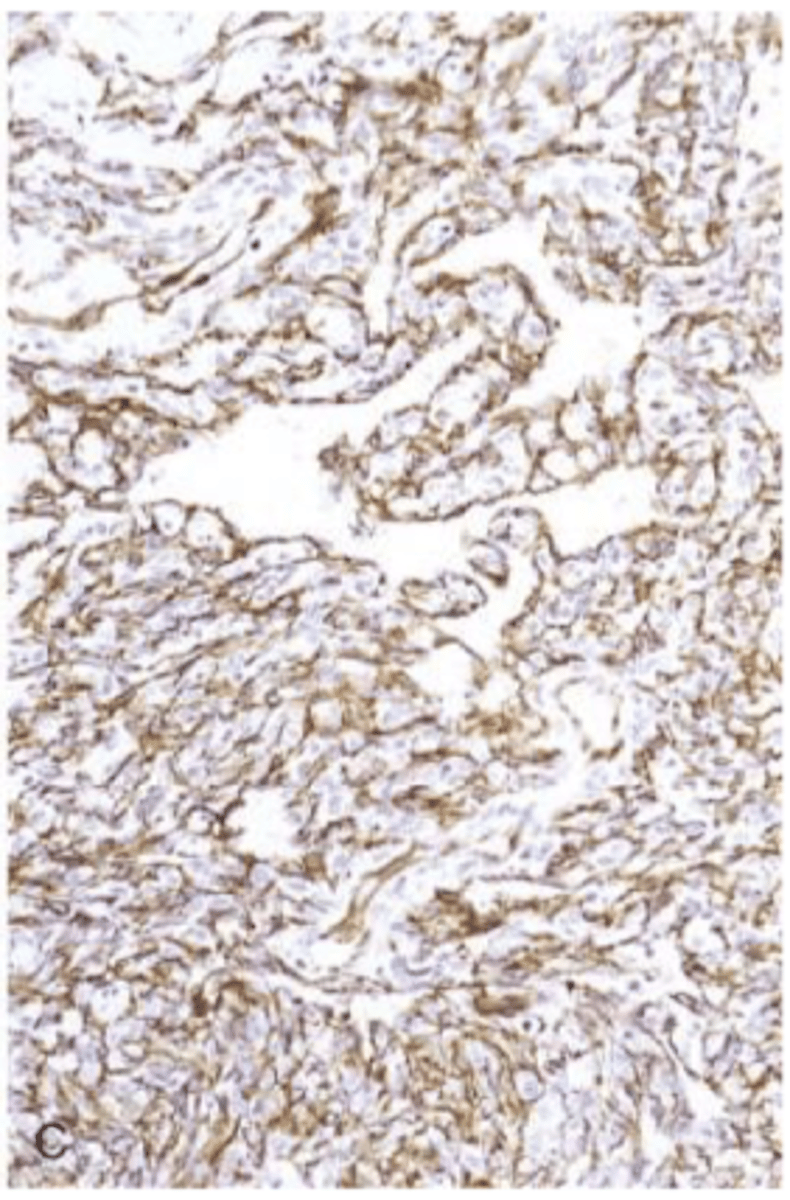

angiosarcoma

malignant endothelial neoplasm

CD31 (vWF)

endothelial origin

angiosarcoma